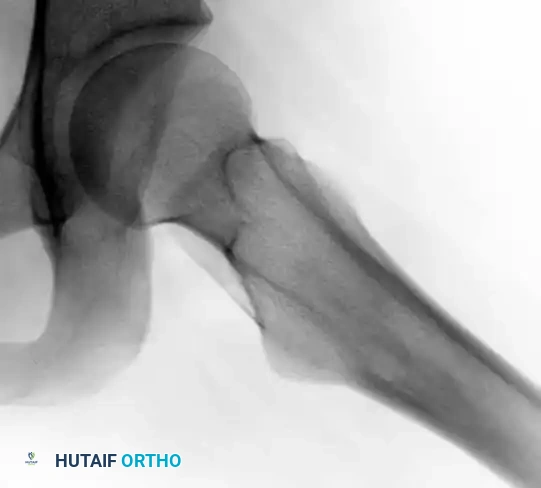

Lateral view of the same left hip, further delineating the reactive cortical thickening characteristic of an osteoid osteoma.

Standard orthogonal radiographs are often sufficient to establish the diagnosis, particularly in diaphyseal cortical lesions. The classic appearance is a small, radiolucent central nidus surrounded by a massive, thick rim of reactive sclerotic bone.

Plain Radiographs:

Imaging studies are usually definitive, and a biopsy is rarely required to confirm the diagnosis prior to definitive treatment. The diagnostic criteria hinge on identifying the central nidus, which by definition is less than 1.5 cm in diameter. Lesions identical in histology but larger than 1.5 cm are classified as osteoblastomas.